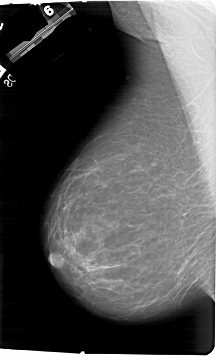

A_1177_1.RIGHT_MLO

LEFT_CC LINES 6151 PIXELS_PER_LINE 4261 BITS_PER_PIXEL 12 RESOLUTION 43.5 NON_OVERLAY